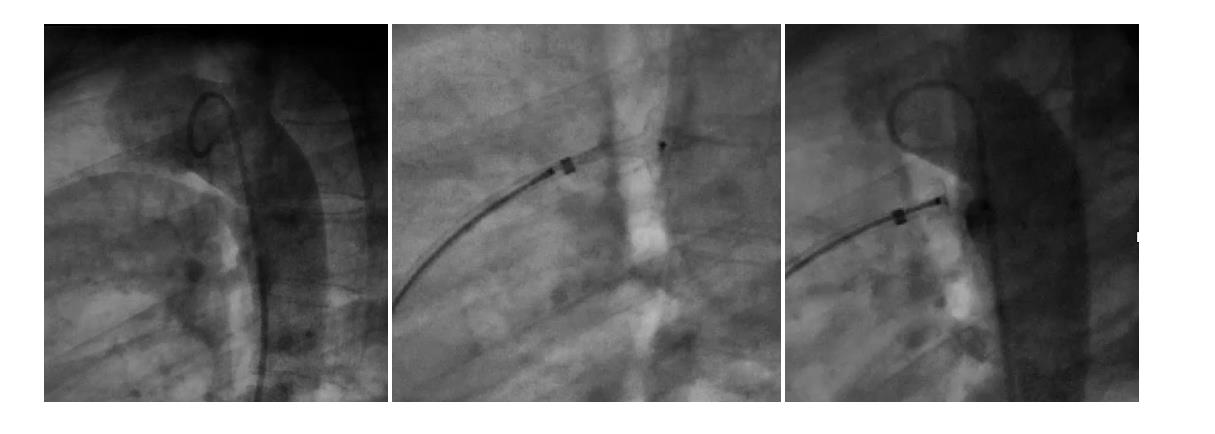

当院では、特に成人先天性心疾患(ACHD:Adult congenital heart disease)の方の診断、治療、手術に取り組んでいます